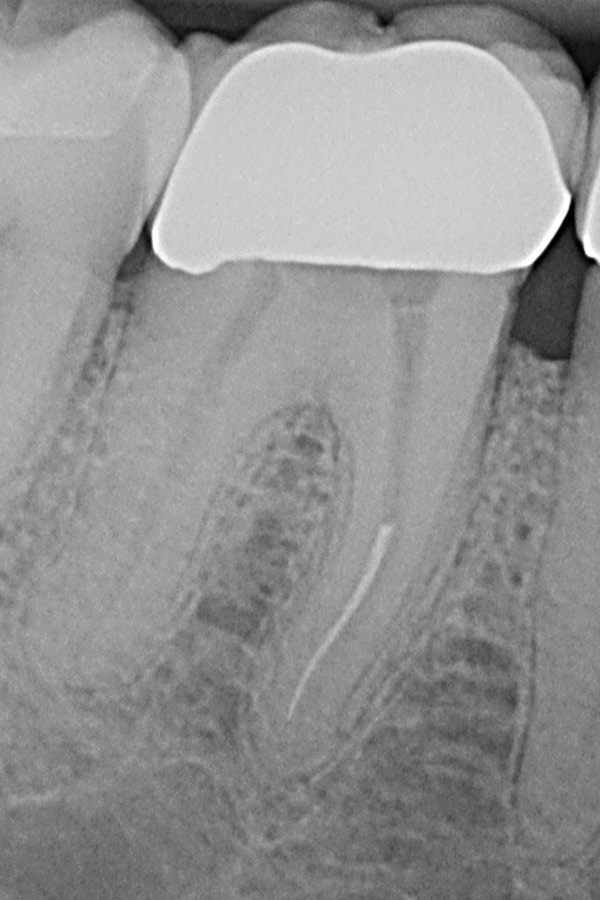

Unvollständige Wurzelfüllungen in zwei Unterkiefer-Prämolaren

Nach Revisionsbehandlung der stark verzweigten Wurzelkanäle

Unterkiefer-Molar mit unvollständiger Wurzelfüllung und Zahnwurzelentzündung

Ausgeheilte Entzündung 1 Jahr später nach Revisionsbehandlung